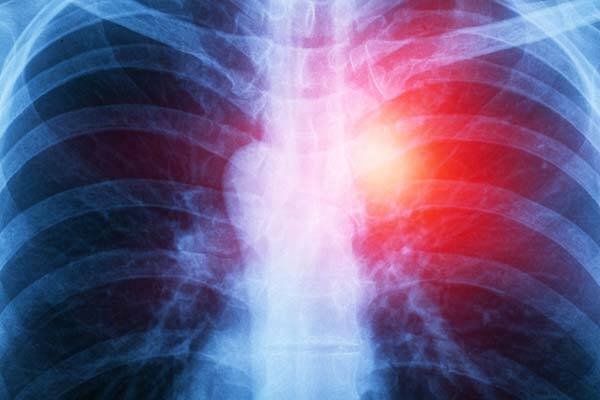

Mesothelioma affects almost every human body area, like the heart, brain, lungs, arms, chest, stomach, etc. It can also predispose you to numerous infections. The disease causes weight loss, fatigue, abdominal pain, fever, anemia, bowel obstruction, etc. Other physical symptoms include persistent cough, shortness of breath, and painful breathing.